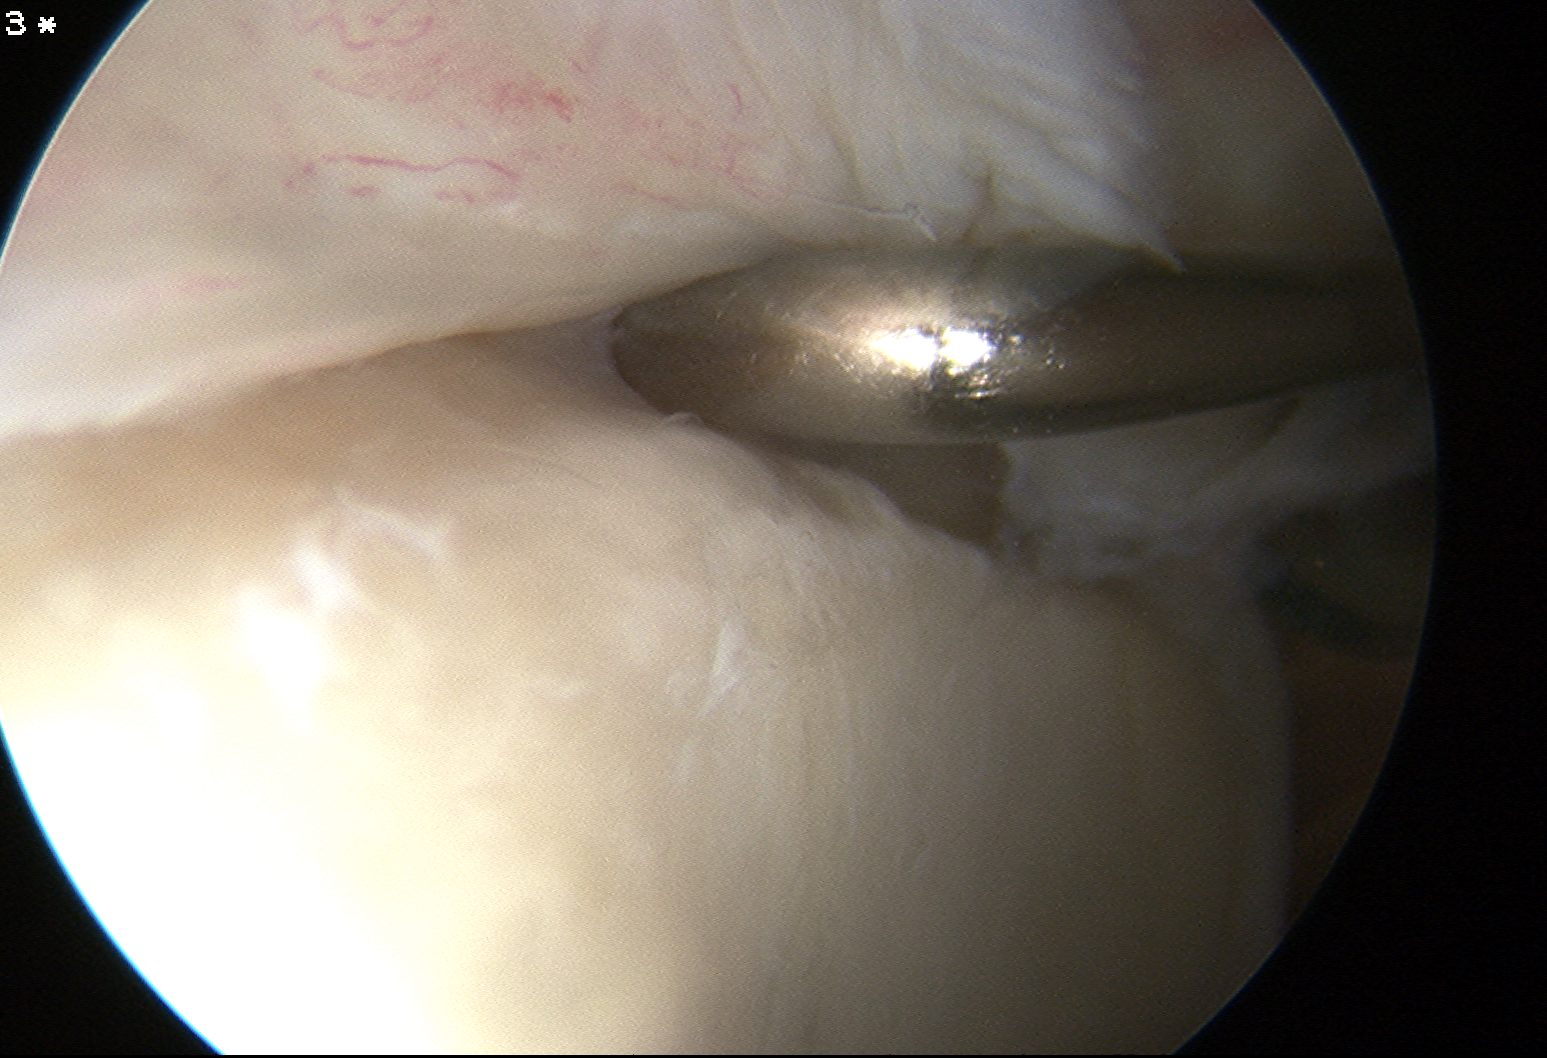

Arthroscopy

Normal insertion of superior labrum onto glenoid

Sublabral foramen / recess

Normal variant

- recess under superior labrum

- this area of glenoid has no evidence of trauma with normal cartilage

- superior labrum and biceps anchor intact and stable

Sublabral foramen with stable biceps anchor